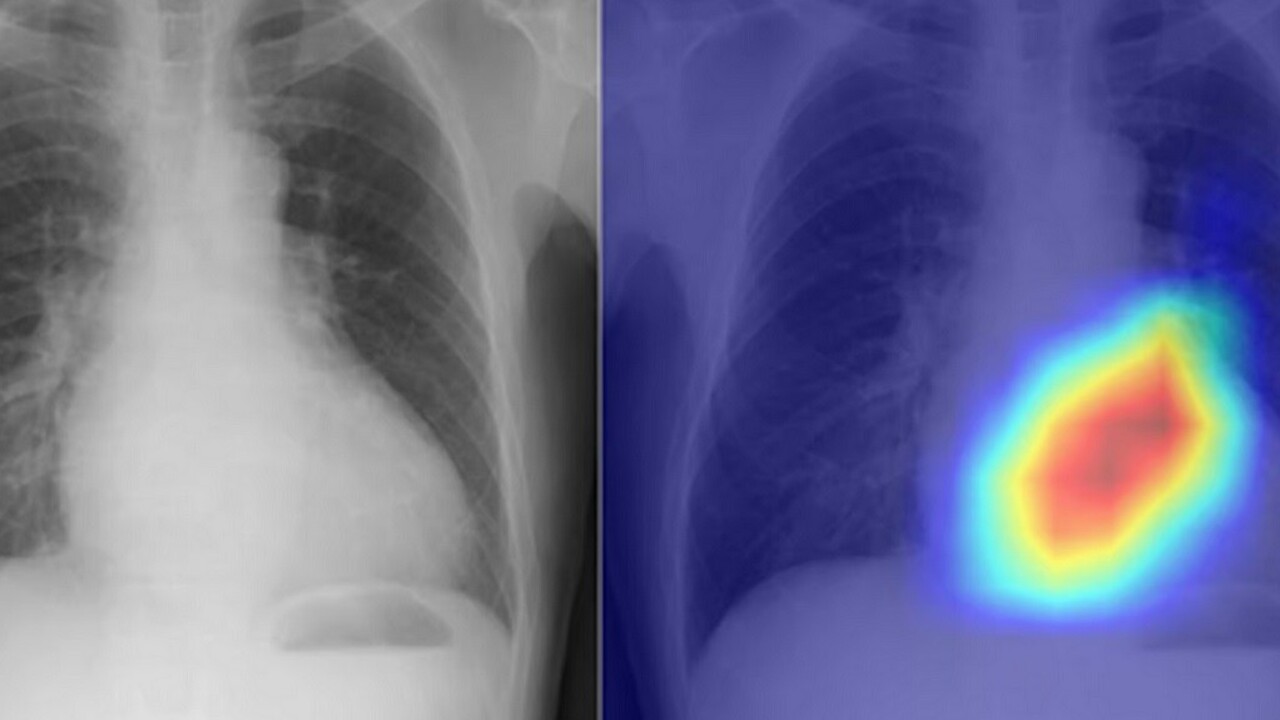

Umelá inteligencia mení röntgen hrudníka na lepší diagnostický nástroj

Rádiológia ako jedna z oblastí medicíny je vďačná na využitie umelej inteligencie.